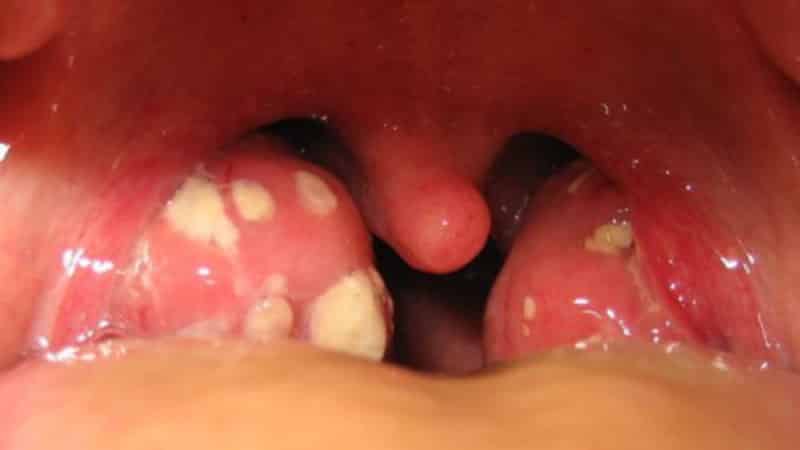

В остром состоянии, во время обострений, можно заметить следующие симптомы, схожие с ангиной:

- резкое повышение температуры тела;

- постоянная боль в горле, усиливающаяся при глотании;

- увеличение и отек миндалин;

- появление характерных белых налетов на гландах;

- увеличение и болезненность лимфатических узлов, расположенных рядом с воспалением.

При осмотре горла врач может заметить: миндалины увеличены и имеют рыхлую структуру. Небные дужки могут отекать и сливаться с миндалинами. Если при надавливании на миндалины появляются гнойные выделения или творожистые пробки, это является уверенным признаком тонзиллита.